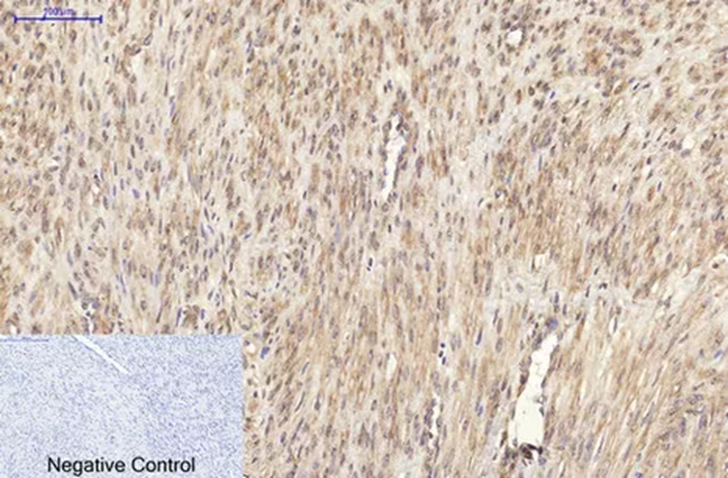

目前最受歡迎和認可的增殖標記是Ki-67(Cat No. ABM40064)(全名MKI67,marker of proliferation Ki-67),這個分子標記同時也是多種癌症病理診斷指標之一,下圖為人類子宮癌組織的Ki-67免疫組織化學染色。在細胞質、細胞核和細胞膜上均有表達。